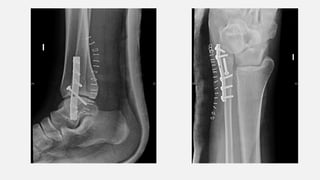

• 14/05/2019  intervingut. Abordatge lateral sobre el peroné. Neteja del focus de

fractura. Reducció i fixació amb pern i fixació amb placa 1/3 canya de 6 orificis.

RX TURMELL AP i LAT (16/07)